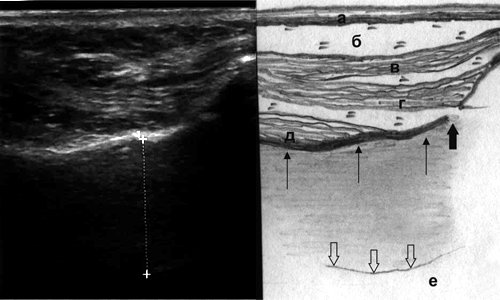

Мягкие ткани собачьей ямки представлены кожей, подкожножировой клетчаткой и мимическими мышцами (рис. 2). Наиболее поверхностно располагается m. levator labii superioris alae nasi, идущая от нижнемедиального края глазницы к верхней губе, на эхограмме видно только ее брюшко, так как место отхождения остается вне среза. Срединное положение занимает m. levator labii superioris, начинающаяся от всего подглазничного края верхней челюсти, пучки мышцы сходятся книзу и вступают в толщу мышцы, поднимающей угол рта и крыло носа. Наиболее глубоко расположена m. levator anguli oris, начинающаяся от дна клыковой ямки и прикрепляющаяся к углу рта.

Рис. 2. Эхографическая картина верхнечелюстной пазухи при остром катаральном синусите, сагиттальный срез: а - кожа, б - подкожная клетчатка, в - m. levator labii superioris alae nasi, г - m. levator labii superioris, д - m. levator anguli oris, толстая стрелка - foramen infraorbitalis, тонкие стрелки - передняя стенка пазухи, полые стрелки - дистальный контур утолщенной до 16 мм слизистой оболочки, е - воздух.

Ниже места отхождения m. levator labii superioris гиперэхогенная линия, являющаяся отражением костной поверхности, имеет небольшой "дефект", соответствующий подглазничному отверстию (foramen infraorbitalis), через которое из подглазничного канала выходят одноименные нерв и артерия.

При отеке слизистой оболочки верхнечелюстной пазухи за ее передней стенкой отмечается появление зоны пониженной эхогенности однородной структуры с достаточно четким дистальным контуром толщиной от 0,5 до 1,6 см (см. рис. 2).